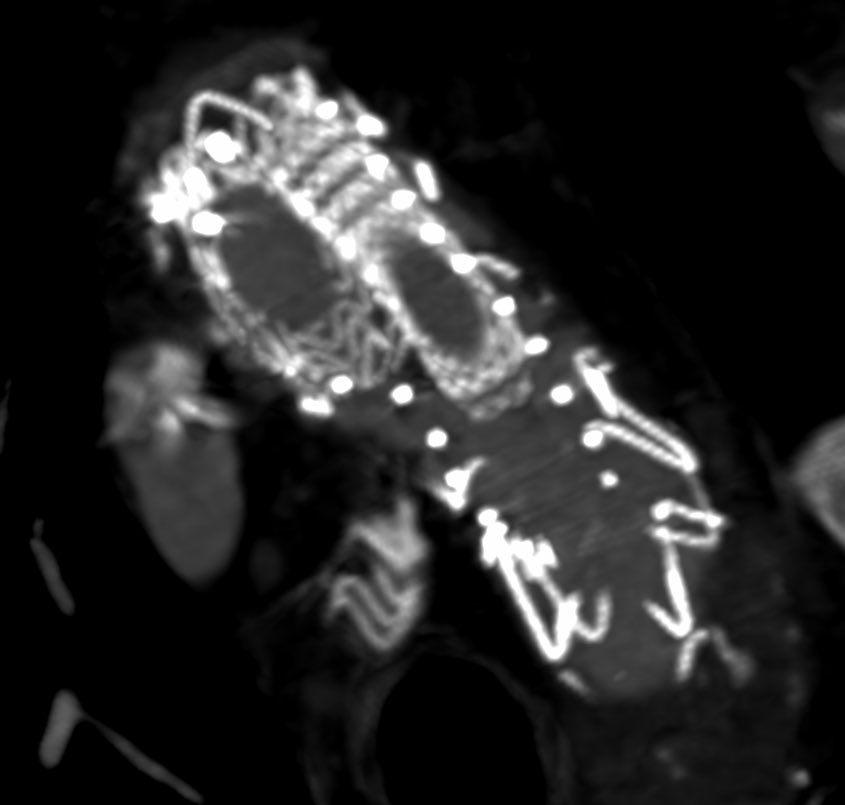

Type 1A endoleak with a short ascending graft and expanding arch. Our team’s first experience using the Bolton Arch graft. Really precise deployment and easy cannulation of the tunnels @TerumoAortic @CAIRweb #aorta